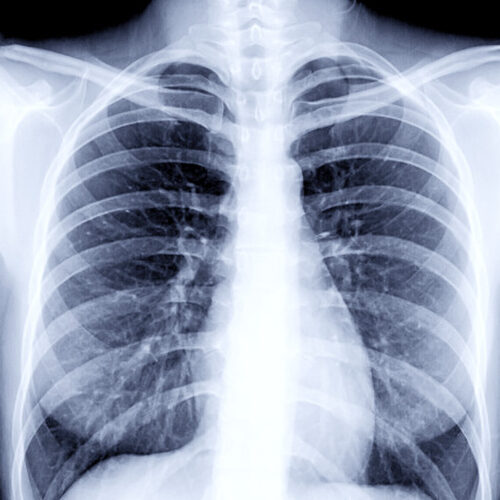

We have a huge number of cases with different modalities and regions

By Modality